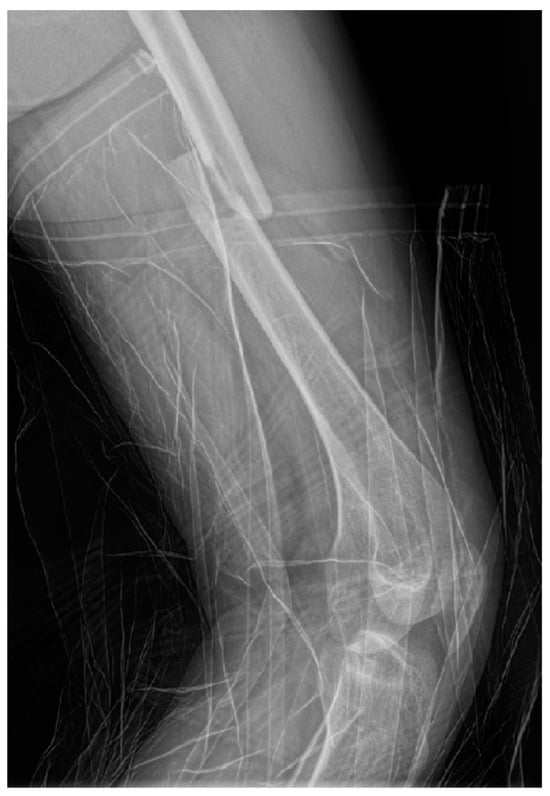

Surgical intervention was performed by a multidisciplinary team: an anesthetist, an obstetrician, a neonatologist, and an orthopedist. She underwent spinal anesthesia utilizing 0.5% bupivacaine, with the extraction of a healthy female baby, weighing 3200 g, with an Apgar score of 9 by C-section and bilateral tubal ligation at the request of the patient, followed by a successful fracture repair under intraoperative C-arm fluoroscopy. The surgical intervention for the fracture of the femur consisted of closed reduction and osteosynthesis with an anterograde intramedullary nail locked proximally and distally with a screw. The postoperative X-ray control revealed good fracture reduction and correct placement of the osteosynthesis material (Figure 2 and Figure 3).

Figure 3.

Postoperative anteroposterior view of the left thigh—distal pole of the intramedullary anterograde nail fixed statically with one screw.